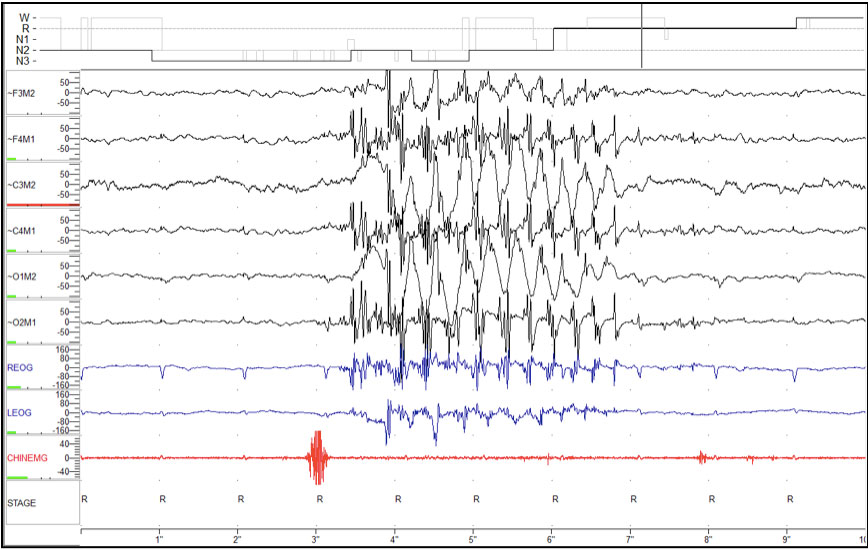

Figure 1: 30-second epoch during REM sleep showing repetitive movements with a frequency of 3 Hz.

Figure 2: 10-second epoch during REM sleep, demonstrates movement artifact on EEG channels with a frequency of 3 Hz.

While this patient’s behavior appears at first glance to be consistent with RMDS arising from REM sleep, further inspection reveals that the frequency of her movements (3 Hz) was faster than that typically described with RMDS (Figures 1 and 2). Additionally review of this patient’s other epochs of REM revealed the presence of frequent RSWA, both during her diagnostic polysomnogram and during the positive airway pressure (PAP) titration study (Figure 3)